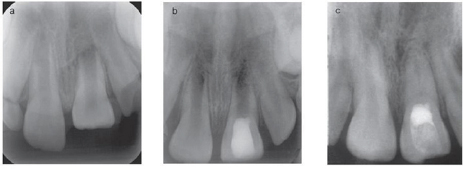

Figure 5: Pulpotomy in lower molar.

a) Preoperative radiograph with extensive decay and open apex.

b) After removal of caries and perform pulpotomy and resorted with amalgam.

c) Postoperative radiograph after periapical tissue healing and apex closure.

Figure 6: Calcium hydroxide and pulpal responses.

a) Exposed pulp, b) The high PH generates a zone liquefaction necrosis and a zone of coagulation necrosis, c) Sperical foci of calcification are formed that coalesce to form calcification zone and next to that collagen is formed, d) Bone like tissue is deposited containing cells and vascular inclusions.

Figure 7: Mineral trioxide aggregate and pulpa! responses.

a) High PH generates a very narrow zone of coagulation necrosis,

b) Next to that zone reparative dentinogenesis zone is formed.